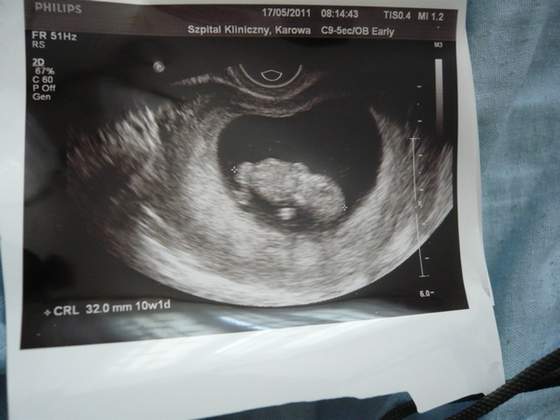

Ja dzis tez juz po wizycie u lekarza, z naszym maluszkiem wszystko bardzo dobrze. Tylko znow male zmiany co do wieku dziecka i terminu porodu. To przez te moje dlugie cykle jak Wam to ostatnio pisalam. A wiec teraz termin porodu zostal przeniesiony na 15.12 (wiec prosze Was dziewczyny o mala zmiane na liscie grudniowych mam)

Zdjecie tez juz mam i o dziwo ja juz dzis mialam robione usg przez brzuszek;-)

A oto i nasz skarb!